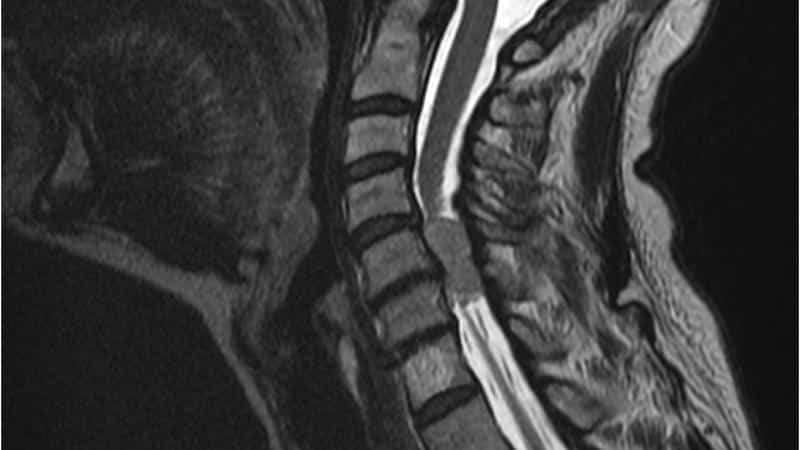

Если специалист обнаружит какие-либо отклонения, он направляет пациента на дополнительные исследования. Обычно менингиома позвоночника выявляется с помощью следующих методов диагностики:

- МРТ.

- КТ.

На сегодняшний день наиболее точным методом диагностики считается МРТ, однако стоимость этой процедуры достаточно высока.